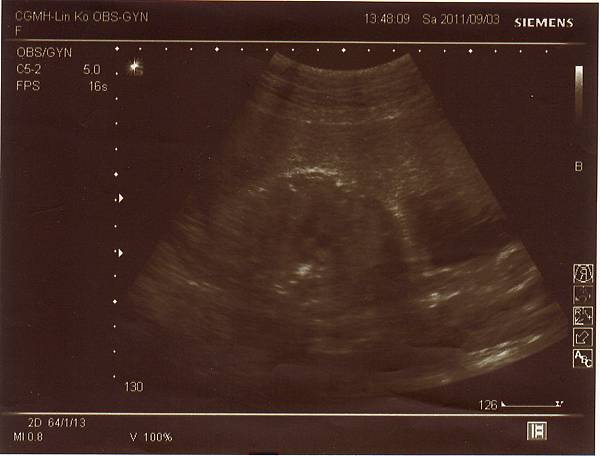

2011.09.03 兔寶妹已經三十週囉!

不僅胎位已經正了(醫生還說姿勢一百),體重也很正常來到1400公克,

連醫生都說看起來肚子不大但孩子卻長得很好呢!